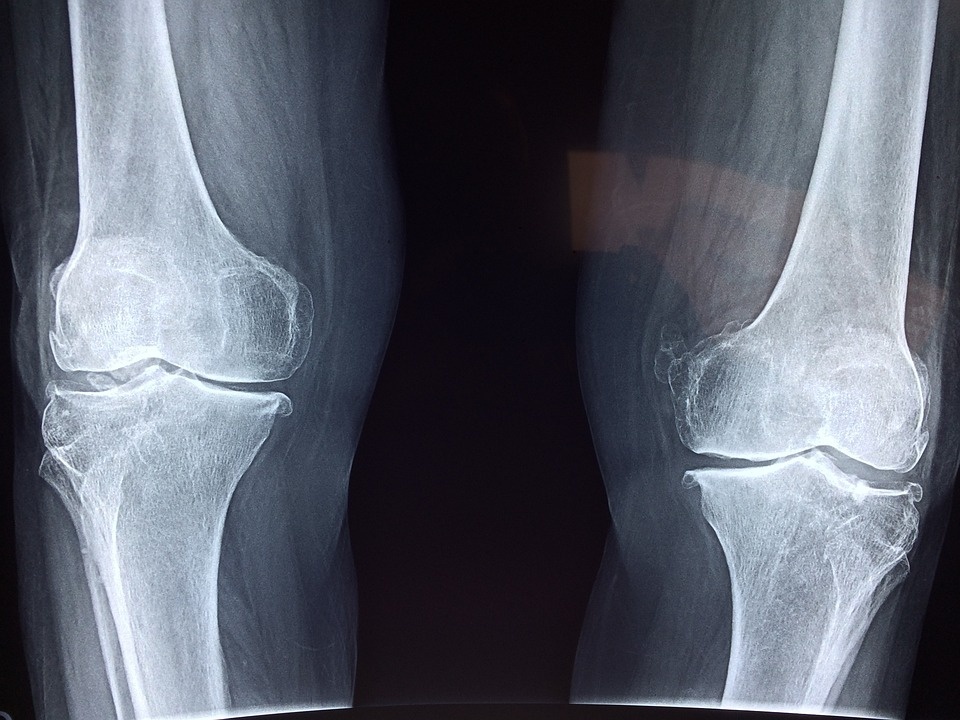

Home » Products » Pagets Disease